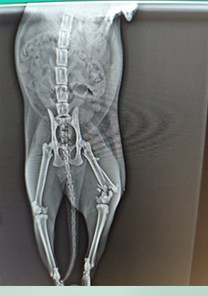

Muhammed Bey'in Kedisi

Muhammed Bey'in kedisi, beşinci kattan düşmeye bağlı olarak tibia ve fibulasında üç parça halinde kırık tespit edilmiştir. Plak uygulaması ile fiksasyonu yapılan kedinin, Operasyonun ardından bir hafta sonra yürüme ve ağrı semptomları tamamen kaybolmuştur. Operasyon günü itibarıyla MN - HUND&KATT kullanılmıştır.